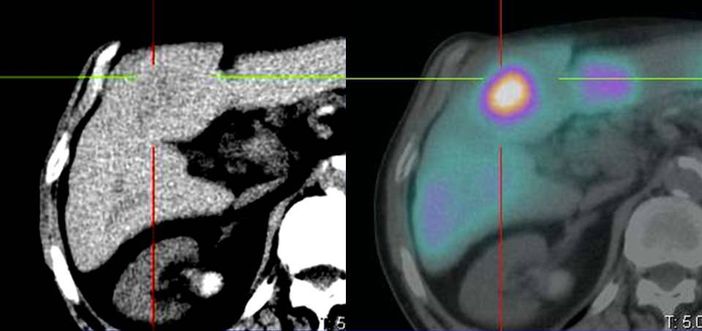

«Tecnicamente - spiega il Dott. Diego De Palma, Direttore della Medicina nucleare - dapprima si procede con uno studio diagnostico mediante un radiofarmaco che, iniettato, permette di evidenziare la dislocazione e la diffusione delle lesioni epatiche, così da valutare la fattibilità del trattamento e stabilire, insieme all’esperto di Radioprotezione della Fisica sanitaria, la corretta attività terapeutica. Successivamente, a distanza di 3-4 settimane, si procede con la somministrazione della terapia, cioè con l'iniezione delle microsfere radioattive».

L'operazione è delicata e si svolge nelle sale di Radiologia interventistica: a seconda della collocazione delle lesioni, il radiologo raggiunge con un catetere l'arteria epatica nel punto più idoneo per colpire in modo mirato. Una volta aperta la strada, è il medico nucleare che somministra le microsfere che, a migliaia, si vanno a posizionare nei vasi capillari che irrorano le lesioni tumorali da distruggere con le radiazioni.